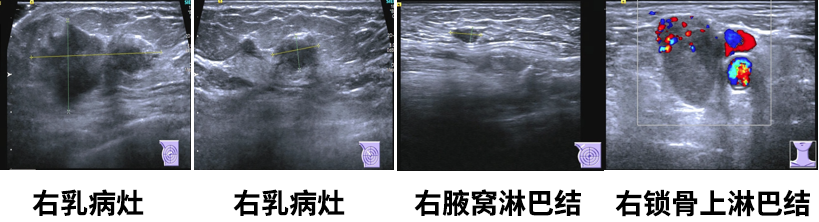

乳腺彩超

1.右乳肿物(约5.0*2.4*4.7cm),乳腺癌可能,BI-RADS5;

2.左乳切除术后,左胸壁未见明显异常;

3.右腋下(1.0*0.5cm)及右侧锁骨上淋巴结(2.6*1.8cm),转移可能。

乳腺MR

右侧乳头后侧中部多个异常信号结节(较大者23*15mm),符合乳腺癌,BIRADS:5类。右侧腋下肿大淋巴结,考虑转移。